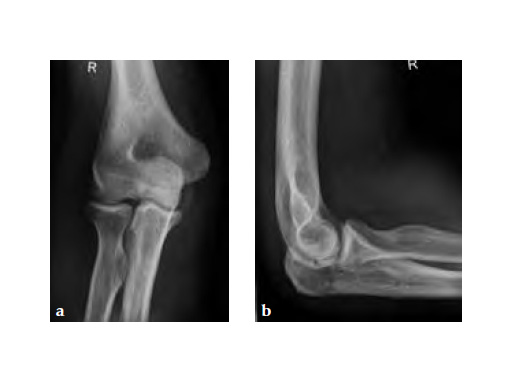

Fig 4ab Implant removal 5.5 months postoperatively.